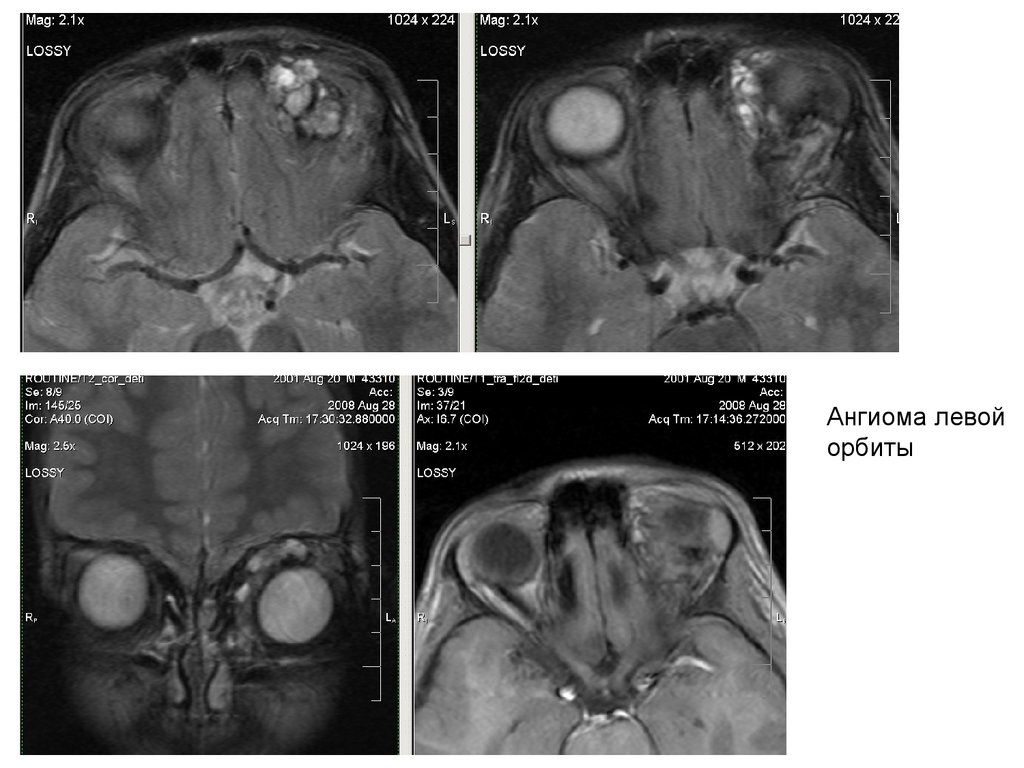

Ангиома левой

орбиты